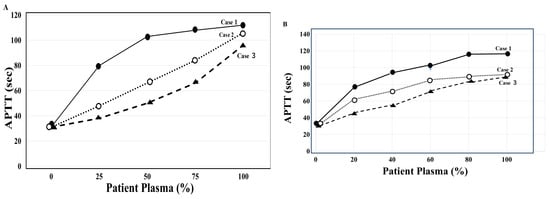

Case 1: The first case comprises a 62-year-old male (Table 1), with the chief complaint of hematoma of the left thigh. His past and family histories showed no bleeding tendencies. The patient was hospitalized due to multiple fractures and nerve injuries from a traffic accident. Two months after the injury, he developed hydrocephalus and underwent VP (ventriculoperitoneal) shunt surgery. Subsequently, he contracted COVID-19 and received treatment, including remdesivir (Gilead Sciences, Foster City, CA, USA), at a rehabilitation hospital to which he had been transferred. Two weeks after the onset of COVID-19, he was admitted to the Hematology Department due to general fatigue and the Appearance of a hematoma on his left thigh, with hemoglobin levels dropping to 4.8 g/dL. Based on prolonged APTT (105 s), FVIII activity < 1%, an inhibitor pattern on a mixing test with normal plasma (both thrombocheck APTT and APTT-SP, Figure 3), and an FVIII inhibitor level of 37.3 Bethesda units (BU)/mL, he was diagnosed with AAFVIIID. He remained stable without bleeding symptoms on prednisolone (PSL, Shionogi & Co., Ltd., Osaka, Japan) monotherapy. Activity recovered to approximately 20–30%, and the patient completed treatment and returned to normal daily activities.

Figure 3.

Cross-mixing test of APTT using normal plasma with thrombocheck APTT (A) and APTT-SP (B) in three cases of AiFVIIID. APTT using thrombocheck-APTT shows a convex upward trend in case 1 but a concave downward trend in case 3. APTT using APTT-SP shows a convex upward trend in cases 1–3, suggesting that the three patients tested positive for inhibitors against the coagulation factor. AiFVIIID, autoimmune coagulation factor VIII (FVIII) deficiency; APTT, activated partial thromboplastin time; closed circle, case 1; open circle, case 2; closed triangle, case 3.

AiFVIIID is diagnosed based on the absence of family and medical histories of bleeding tendency, the potential for massive bleeding, marked prolongation of APTT, significantly reduced FVIII activity, an inhibitor pattern on a mixing test with normal plasma, and confirmation of FVIII inhibitor titers [31,32]. Marked prolongation of APTT and a significant reduction in FVIII activity are initial effective diagnostic measures for suspected AiFVIIID; however, differentiation from hemophilia A is challenging yet essential [3,12]. Therefore, a definitive diagnosis of AiFVIIID is made using FVIII inhibitor titer measurement and a mixing test with normal plasma. In this study (Table 1), inhibitor titers were high in cases 1 and 2; in comparison, those in case 3 were not markedly high. The inhibitor pattern in a mixing test with normal plasma using APTT generally shows an upward convex curve [33]. In this study, an inhibitor pattern was observed in cases 1–3 in a mixing test using APTT-SP; however, when thrombocheck-APTT was used, case 3 did not show an inhibitor pattern. These findings suggest that APTT-SP may be more sensitive than thrombocheck-APTT in diagnosing inhibitors using a mixing test. There are also reports on the effects of APTT reagents on the sensitivity of LA or anticoagulants, making the choice of APTT reagent important for diagnosing AiFVIIID [34,35]. Furthermore, case 3 was complicated by accompanying ET, which could have potentially caused secondary von Willebrand disease [36], and as a result, the mixing test may have shown a factor deficiency pattern.